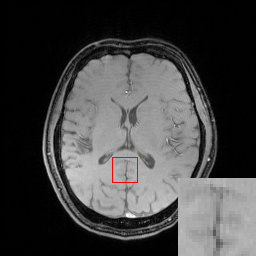

We illustrate with reconstructions for three CS-MRI methods: TLMRI (transform learning MRI) [25], PANO (patch-based nonlocal operator) [23] and GBRWT (graph-based redundant wavelet transform) [14]. The PANO and GBRWT models achieve impressive reconstruction qualities because they use an nonlocal prior and adaptive graph-based wavelet transform to exploit image structures. In TLMRI, the sparsifying transform learning and the reconstruction are performed simultaneously in more efficient way than DLMRI [24]. The three methods represent the state-of-the-art performance in the non-deep CS-MRI models. In Figure 2, we show the reconstructions error for zero-filled (itself a potential reconstruction “algorithm”), TLMRI, PANO and GBRWT on a complexed-valued brain MRI using 30%percent3030\% Cartesian under-sampling. The error display ranges from 0 to 0.2 with normalized data. The parameter setting will be elaborated in the Experiment Section V.

We also consider the deep learning DC-CNN model [26] as the guide module. We also give the reconstruction error in Figure 2. We observe the zero-filled, TLMRI, PANO, GBRWT and DC-CNN models all suffer the structural reconstruction errors, while the DC-CNN model achieves the highest reconstruction quality with minimal errors because of its powerful model capacity. Another advantage of this CNN model is that, once the network is trained, testing is very fast compared with conventional sparse-regularization CS-MRI models. This is because no iterative algorithm needs to be run for optimization during testing since the operations are a simple feed forward function of the input. We compare the reconstruction time of TLMRI, PANO, GBRWT and DC-CNN for testing for Figure 2 in Table I.

Figure 2: The reconstruction error of a brain MRI using zero-filled, TLMRI, PANO, GBRWT and DC-CNN under 1D 30%percent3030\% under-sampling mask.

We evaluate the proposed DECN framework using PSNR and SSIM (structural similarity index) [30] as quantitative image quality assessment measures. We give the quantitative reconstruction results of all the test data on different under-sampling patterns and different under-sampling ratios in Table II. We show the Cartesian 30%percent3030\% under-sampling mask in Figure 6(b) and the Random 20%percent2020\% under-sampling mask in Figure 7(b). We observe that DECN improved all off-the-shelf CS-MRI inversion methods on all the under-sampling patterns. Since the Random mask enjoys the more incoherence than the Cartesian mask with the same under-sampling ratio, the CS-MRI achieves better reconstruction quality on the Random masks. Also, we observe the plain DC-CNN model already achieves good reconstruction accuracy, leaving less structural errors for the error correction module, leading to the limited performance improvement about 0.1 dB on the Random 20%percent2020\% and 30%percent3030\% masks. While for other CS-MRI inversions on various sampling patterns, the improvements are at least 1.5dB or even up to 3.5 dB.

In Figure 6, we show reconstruction results and the corresponding error images of an example from the test data on the 1D 30%percent3030\% under-sampling mask. With local magnification on the red box, we observe that by learning the error correction module, the fine details, especially the low-contrast structures are better preserved, leading to a better reconstruction.